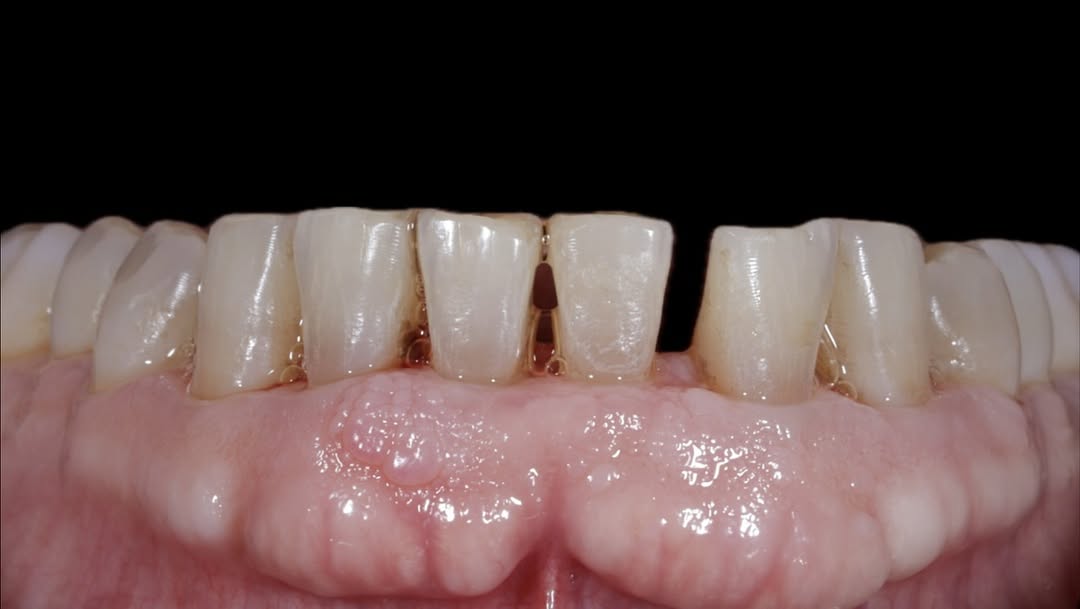

Se presenta un caso clínico de restauración directa en resina composite, ejemplo del valor de la precisión y la técnica meticulosa incluso en procedimientos considerados rutinarios dentro de la práctica diaria. El caso pone en evidencia la importancia del control de la morfología, la textura y la integración cromática, así como del adecuado aislamiento del campo operatorio y la estratificación del material, factores determinantes para conseguir un resultado natural, funcional y duradero. A través de una ejecución cuidadosa, se logró una restauración estéticamente imperceptible y funcionalmente estable, que respeta los principios de mínima invasión y adhesión efectiva. Este tipo de procedimientos, aunque cotidianos, reflejan la constancia y el nivel de exigencia clínica necesarios para ofrecer odontología de calidad en todos los casos, independientemente de su complejidad.